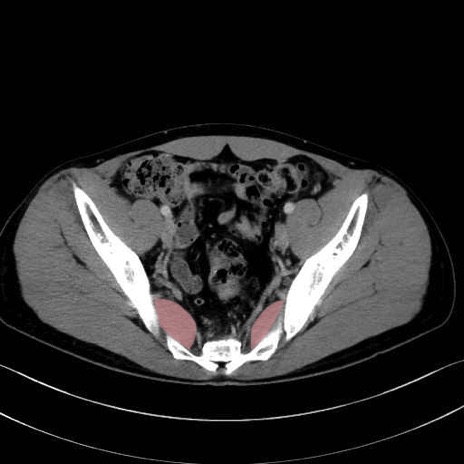

梨状筋 (Piriformis)